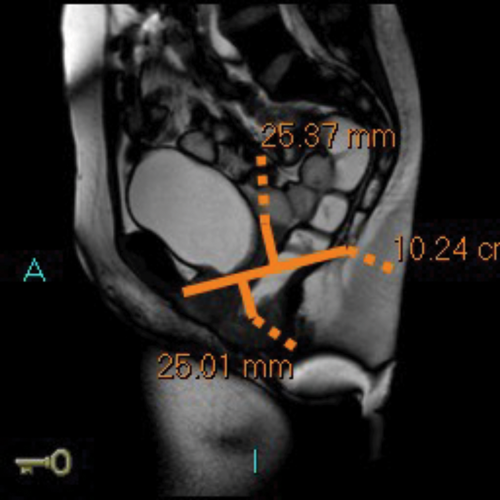

MR defecating proctograms are performed in a 1.5 Tesla MR scanner (Philips Sense). A similar detailed explanation of the procedure and consenting process takes place, so the patient knows what to expect during the three ‘cine’ scans of ‘squeeze up’, ‘bear down’ and ‘empty out’. The urinary bladder must be empty as far as possible during the MR scan.

After an initial digital rectal examination, 120mls of ultrasound jelly is instilled into the rectum via a rectal tube with the patient in the left lateral position. The patient is then turned to lie supine and positioned so that the top of the Sense-body coil is at same level with the iliac crest. The MRI scan protocol includes T2 axial and coronal sequences and sagittal ‘cines’ squeeze, bear down and two defecatory attempts with a couple of minutes rest in between. In cases of incomplete evacuation, a repeat evacuation may be needed or a coronal cine.

In addition the anterior and middle compartment is assessed, particularly for the presence and anatomy of a cystocoele or vault prolapse. The T2 sequences also allow pelvic evaluation for other incidental pathologies (Figure 2).

Figure 2d: Large rectocoele on MR proctogram.